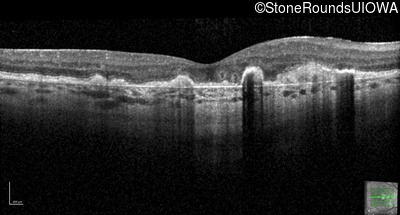

Malattia Leventinese (IIJ)

Malattia Leventinese (IIJ)

This 43 year old woman has experienced a gradual reduction in her central vision for the past 3 years.

| Malattia Leventinese | EFEMP1 | Arg345Trp CGG>TGG | AD |